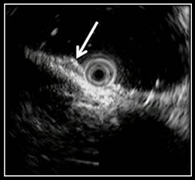

Рис. 5 (а, б). Эндосонографическая картина полиповидной формы НЭО желудка

Полиповидную форму НЭО желудка эндосонографически разделяют на два типа по преимущественному характеру роста опухоли:

— экзофитный — гипоэхогенное образование, исходящее из уровня мышечной пластинки слизистой оболочки, выступающее в просвет желудка (эндогастрально), наружный контур мышечной пластинки слизистой оболочки четко дифференцируется; подслизистый и мышечный слои не вовлечены в опухолевый процесс (рис. 5а).

— смешанный (экзофитно-инфильтративный) — у данного типа НЭО сочетаются как эндогастральный компонент опухоли, так и инфильтративный рост, распространяющийся от основания образования на уровне мышечной пластинки слизистой оболочки на подслизистый слой (рис. 5б).